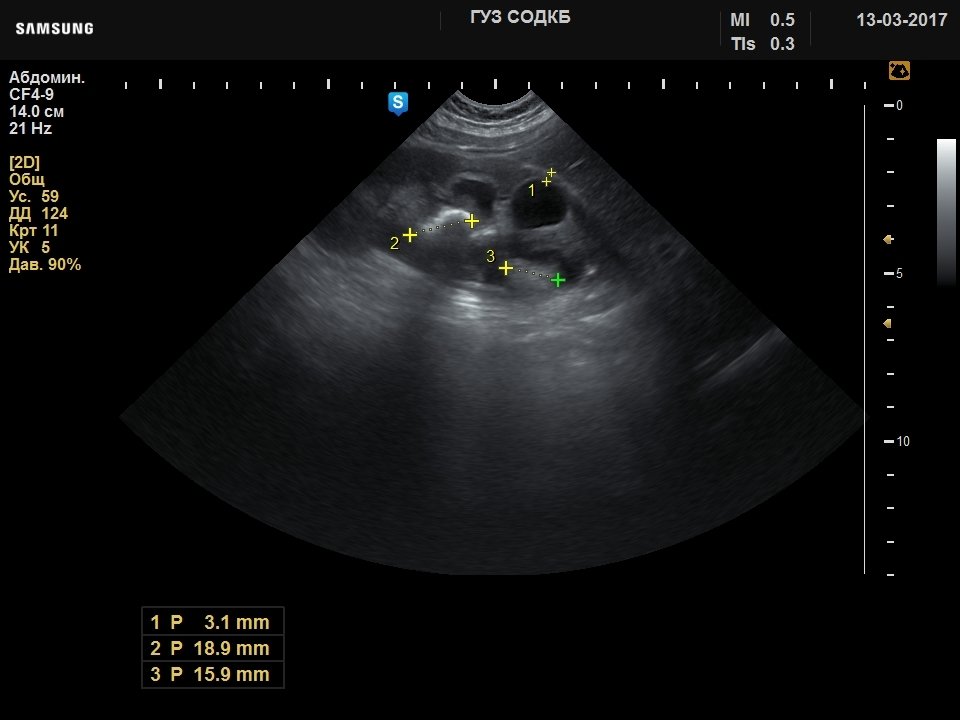

[RU] Ultrasound image №738: Kidney stones and dilated renal pelvis in a child 6 months old. Microconvex probe 4-9 MHz (neonatal), B-mode.

Author: Sukhanov S.A., Saratov.

Echogramm was received by ultrasound scanner H60 (out of production).